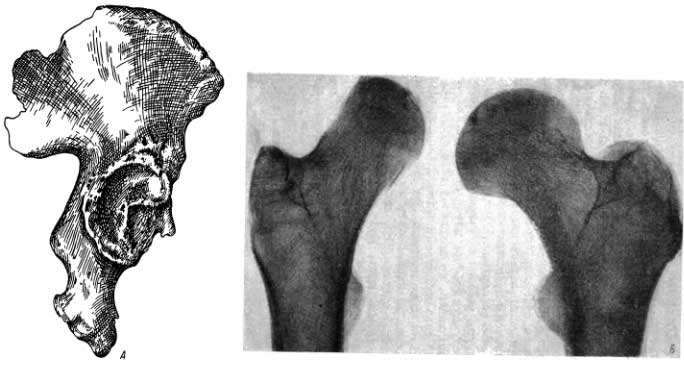

Рентгеновские снимки и визуализация болезни Педжета

Раздел: Мудрость в объективе